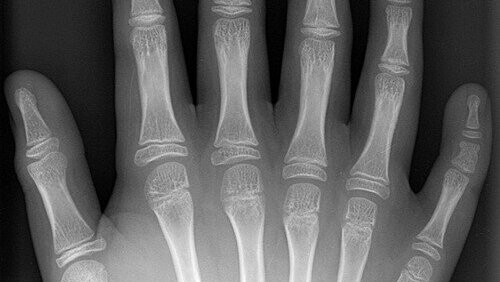

Полидактилия кисти. Разбираемся какие бывают.

Врожденная полидактилия кисти. Странное название деформации, так как приобретённую полидактилию представить себе очень сложно. Я постараюсь доступно рассказать какие виды полидактилии бывают и что в каждом случае делаю чтобы исправить. И так, начнём. Полидактилия - это врожденная деформация при которой отмечается увеличение количества сегментов кисти. Что такое сегмент? Пальцы бывают трёх фаланговые (со второго по пятый) и двух фаланговые (первый или большой). Каждая фаланга - сегмент. Существует понятие - луч кисти...

Полидактилия.

Доводилось ли вам встречать животных, у которых на передних или на задних лапах было больше пальцев, чем нужно? Такое явление называется полидактилией и описано у человека, кошек, собак и др. 📍Полидактилия – это врожденная аномалия, характеризующаяся большим, чем в норме, количеством пальцев. В большинстве случаев это генетически обусловленная патология, хотя есть сообщения о появлении потомства с полидактилией у животных без подобной особенности, то есть приводить к полидактилии могут еще и нарушения...